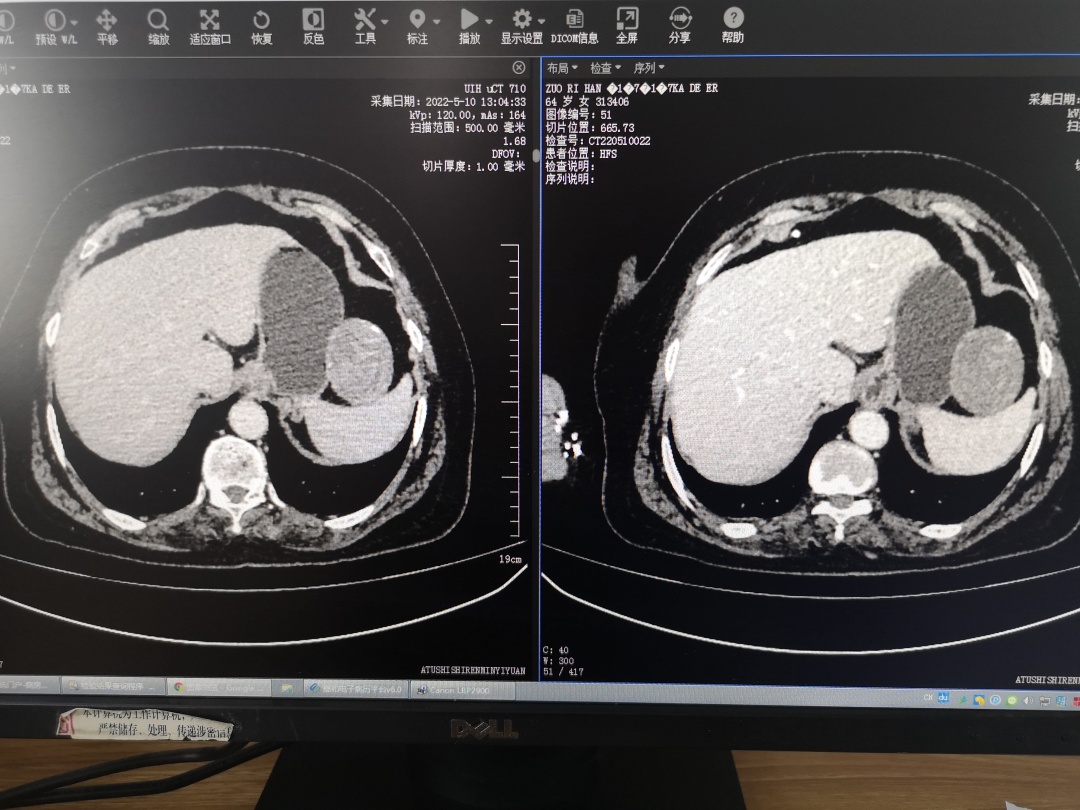

5月中旬的一天,64岁的维族大姐左日汗卡得尔因健康体检后发现“胆囊结石”住院,要求行胆囊切除术。住院后,完善术前检查时床位医生发现患者左上腹部脾脏和胃之间有一直径约10cm的不明性质肿块。了解病情后患者和家属非常焦虑,找到外一科昆山援疆专家王恒杰咨询。“以前在我们这边遇到这种情况,一般都会选择直接去喀什或者乌鲁木齐等大型三甲医院治疗。”患者家属说,“跟医生沟通后,知道有昆山援疆医疗团队救治保障,我们放心很多,决定留在阿图什市人民医院手术。”

考虑到患者胆囊结石合并腹腔肿瘤,且体态较肥胖并伴有基础疾病,手术风险较大,医务科主任张志豪组织昆山援疆专家放射科主任黄敏、麻醉科主任王铁和科室同仁进行术前MDT,为病人制定最佳治疗方案,即实施腹腔镜手术治疗,一次手术同时解决右上腹部胆囊和左上腹部肿瘤两个问题。术中,考虑到脾脏质地软脆,稍有不慎即会导致撕裂加重引起无法控制的大出血,甚至危及生命,遂决定采用超声刀小步快走、分层推进结合电棒隔小纱块烧灼止血的方法分离肿瘤,经过2个多小时细致入微的努力,成功摘除了腹腔肿瘤,随后对胆囊实施了切除术。“手术方案很详细,术中王恒杰还为科室同仁讲解分离要点、牵拉力度和其他手术注意事项。”阿图什市人民医院专家阿布都外力阿布力孜说,“经过王恒杰耐心细致地康复指导,患者病情恢复很快,胃肠功能已基本恢复,已经顺利出院。”